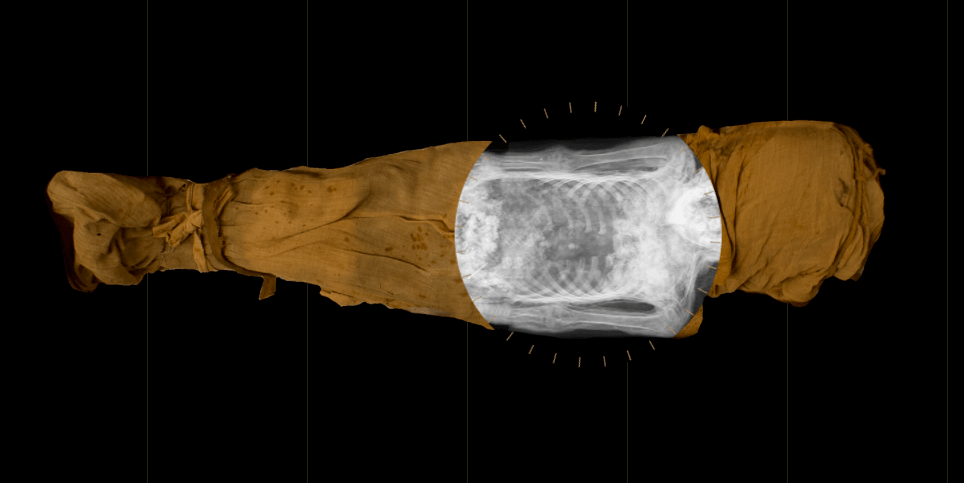

An international and interdisciplinary team, led by David Howard, a professor of electronic engineering at Royal Holloway, used computed tomography (CT) scanning technology to measure the dimensions of the vocal tract of Nesyamun, a mummy that’s spent about two centuries on display at Leeds City Museum in the United Kingdom.

The team then used those measurements to 3D-print an artificial vocal tract, through which they produced sounds using a peculiar electronic device called the Vocal Tract Organ. (You can check it out here.)